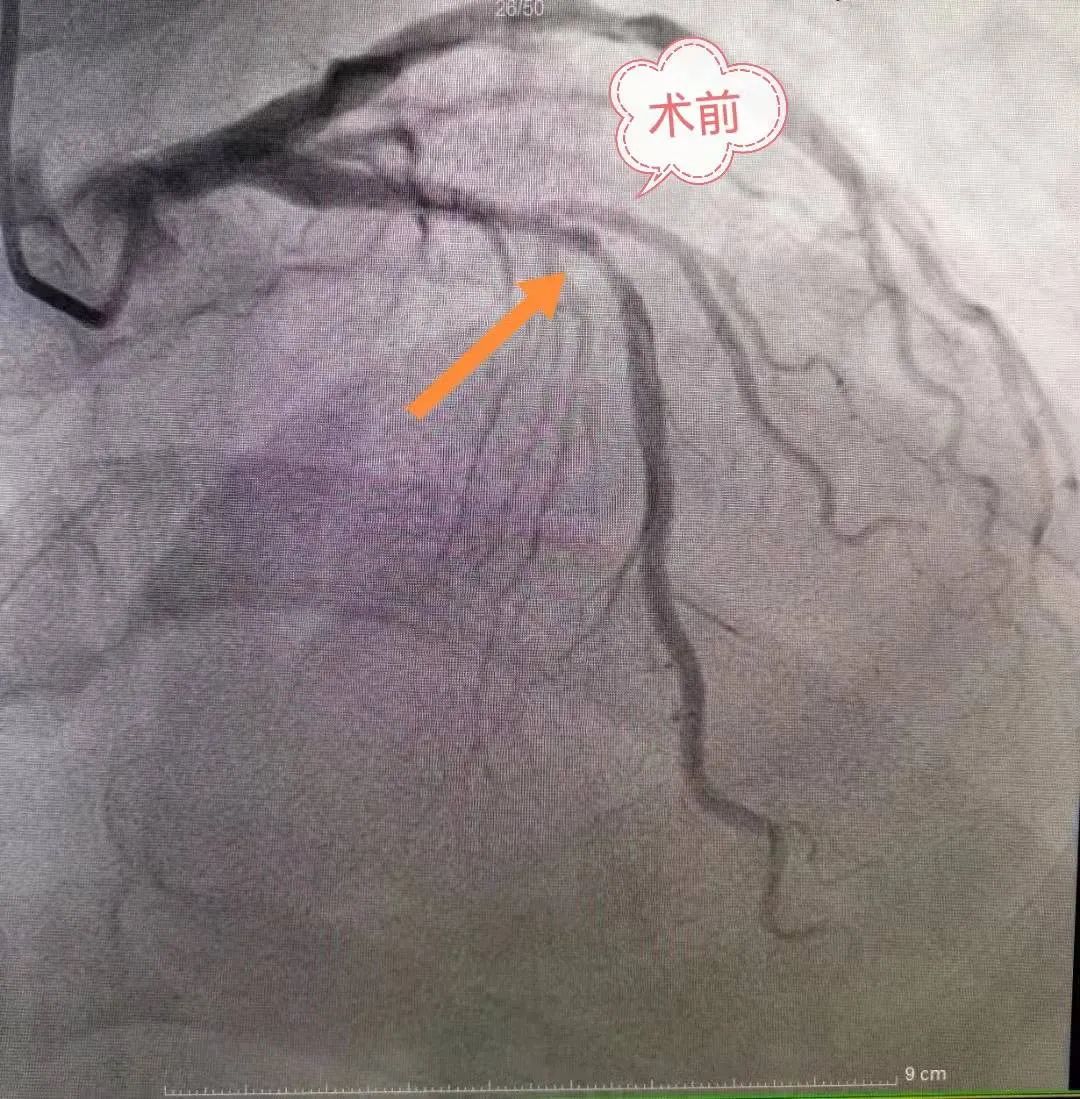

冠脉支架植入术是一种机械性的介入治疗手段,是处理急性冠状动脉闭塞最有效的手段,主要适用于急性心肌梗死、冠状动脉重度狭窄的病人;它是将药物洗脱金属支架永久性地置放于冠状动脉病变处,经球囊扩张释放或自膨胀方式支撑住血管壁,以保持冠状动脉管腔的开放,减轻局部心肌的坏死,降低急性心肌梗死的死亡率。

在DSA开机启用的背景下,我院介入导管室的成立填补了心内科、神经內科、神经外科等多学科介入治疗的空白,提升了我院综合救治能力,真正打造救命的“高速公路”。介入导管室成立至今,共开展冠脉动脉造影术、冠状动脉内支架置入术168台,经股动脉插管全脑动脉造影术8台,手术总费用达80万余。科学有效的护理干预是保障手术顺利进行的重要策略,追求严格的护理操作和耐心细致的心理疏导,为广大患者提供方便、快捷、高效的优质护理服务。